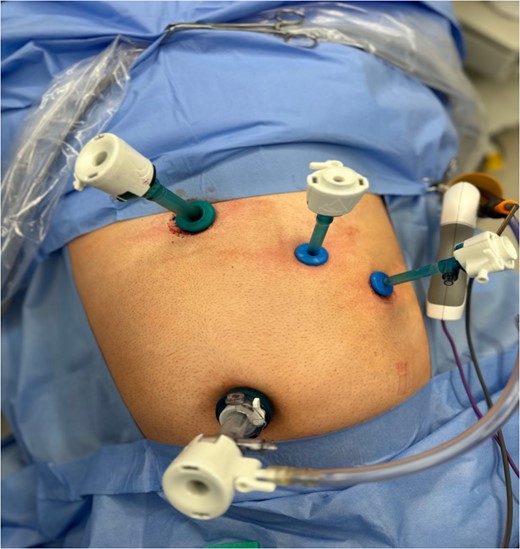

Dissection started with separation of omental adhesions from the fundus of the gallbladder. This was done using a combination of hook diathermy and blunt dissection techniques. Once these adhesions were taken down, Calot’s triangle was identified. Anatomical cross check was performed as usual by identifying segment IV of the liver, Hilar plate, and the hepatic pedicle. Dissection was kept lateral to the ‘line of safety’ and well above Rouviere’s sulcus. The operating surgeon used their right hand for the majority of dissection of Calot’s triangle as usual. Once Calot’s triangle was dissected, two structures were identified going into and out of the gallbladder, and Strasburg’s ‘critical view of safety’ (Fig. 4) was seen [4, 5]. The cystic duct and cystic artery were clipped with three 10 mm endoscopic haemostatic clips and ligated. The 10 mm ligaclipper was inserted through the subxiphoid port and placement of clips was controlled using the surgeon’s left hand. The gallbladder was then dissected from the gallbladder fossa and removed via the umbilical port in a Bert bag.

Critical view of safety with plane of dissection lateral to line of safety; two structures are viewed both entering the gallbladder and the lower border of the gallbladder dissected from the liver.

According to Orozakunov et al, surgeons should be comfortable with the anatomy before dissection and recognize that in SIT, the anatomy is a mirror image [7]. As mentioned in this case, the surgeon performed anatomy checkpoints, which were key to safely performing this case. Before clipping the structures, we ensured that Strasburg’s ‘critical view of safety’ was visible from both the medial and lateral aspects of Calot’s triangle (Fig. 4).